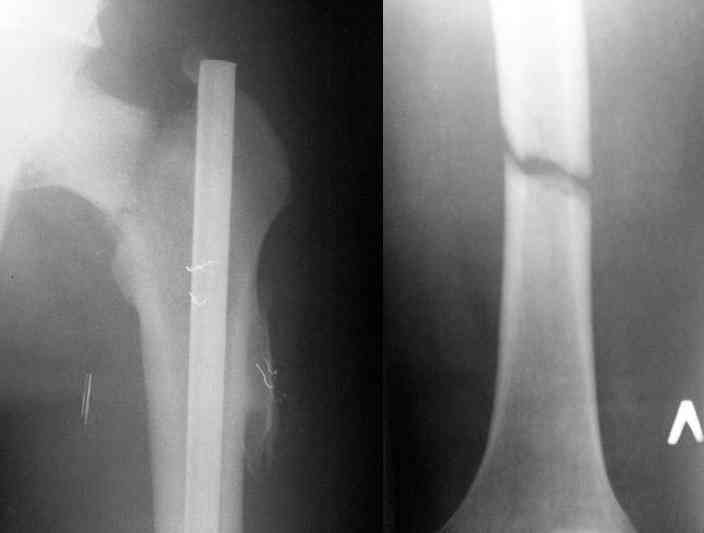

В операционной спереди гвоздя провел два 6.5 мм каннулированных шурупа, также через проксимальное отверстие антеградного гвоздя удалось провести шуруп.

Здесь представлены снимки больного 65 лет, поступившего с диагнозом перелом

бедра после автоаварии.

В первый же день произведено антеградное штифтованием DePuy Trochanteric Nail.

На второй день (7) обнаружен пропущенный перелом,

и проведены шурурпы через и спереди штифта без удаления.

Послеоперационные снимки